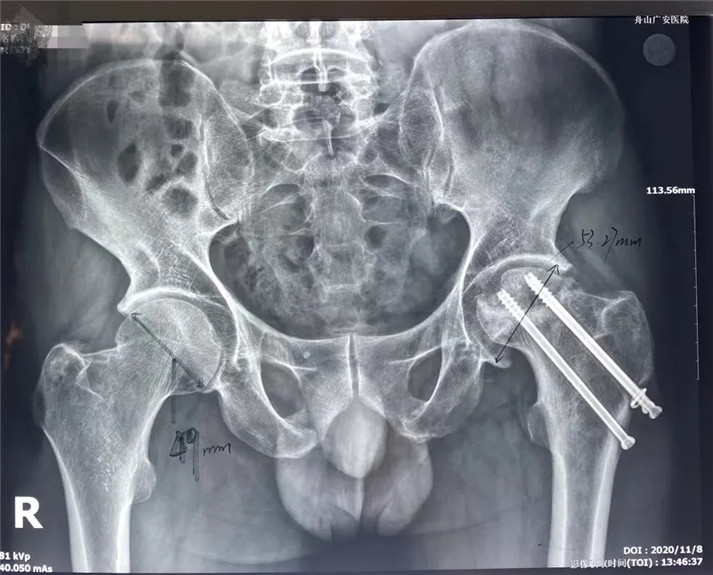

結(jié)合影像學(xué)表現(xiàn)研究后,骨科中心羅軍主任診斷丁先生為左股骨頭壞死,并建議其行全髖關(guān)節(jié)置換手術(shù)。

術(shù)前

考慮到患者的年齡、骨折類型等情況,以及患者的種種擔(dān)憂,為精準(zhǔn)治療、加快愈合、避免關(guān)節(jié)脫位及肢體長短不等,羅軍主任團(tuán)隊采用了近期引進(jìn)的AI HIP置換術(shù)前規(guī)劃系統(tǒng)為患者行術(shù)前規(guī)劃。他們將丁先生的術(shù)前CT數(shù)據(jù)導(dǎo)入到系統(tǒng)中,通過自動識別骨盆和股骨建立了計算機(jī)數(shù)字三維模型。AI HIP顯示患者適合使用合適的髖臼杯、股骨柄、標(biāo)準(zhǔn)陶瓷球頭、陶瓷內(nèi)襯,并精準(zhǔn)定位了截骨線,可以有效幫助醫(yī)生在手術(shù)中做到精確截骨。